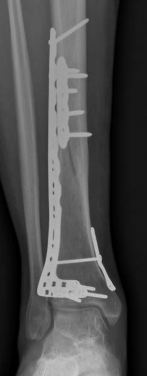

With the articular surface reconstituted, the surgeon's focus shifts to bridging the complex metaphyseal-diaphyseal dissociation. A pre-contoured anatomical locking plate is slid submuscularly or subcutaneously along the diaphysis using a MIPPO technique. The plate is positioned on the anterolateral or medial surface, depending on the preoperative plan and soft tissue constraints.

The distal portion of the plate is secured to the reconstructed articular block. It is imperative that the distal locking screws are placed parallel to the joint space, forming a rigid subchondral raft that supports the articular cartilage. Fluoroscopy is utilized extensively to ensure no screws have penetrated the joint. Once the distal block is secured to the plate, the diaphyseal segment is aligned. Length, alignment, and rotation are restored using manual traction or the femoral distractor. The proximal portion of the plate is then secured to the diaphysis using a combination of non-locking screws (to pull the bone to the plate) and locking screws (to create a fixed-angle construct). The working length of the plate is maximized by leaving several screw holes empty over the zone of comminution, promoting secondary bone healing.